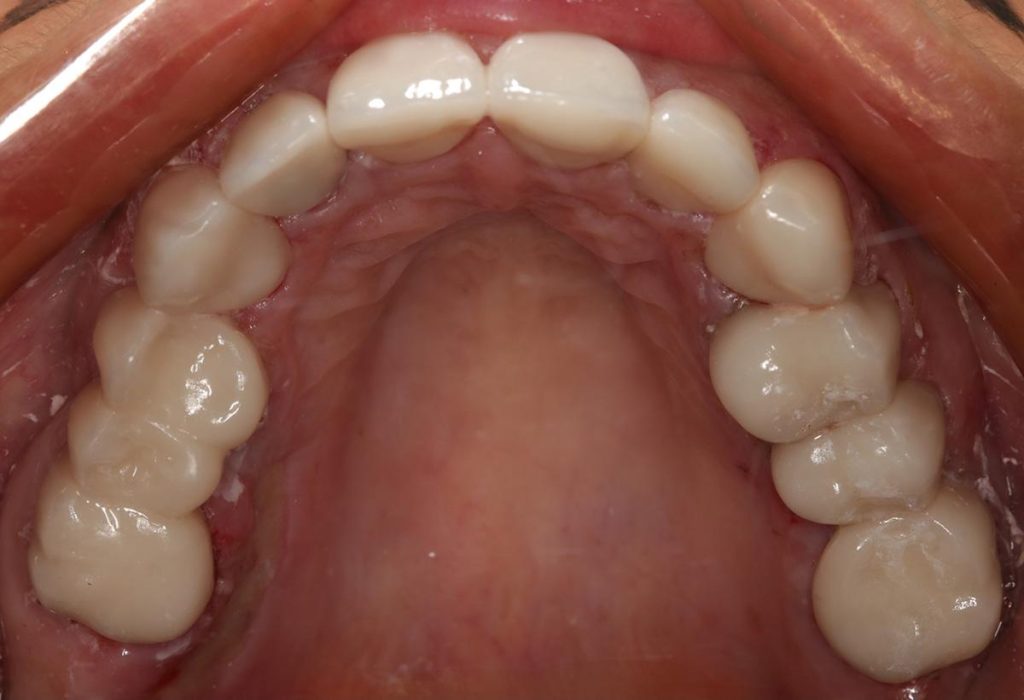

Pod opieką Agnieszki Łukowicz, Master of Science Orthodontics została poddana zaawansowanemu leczeniu aparatem stałym ligaturowym, Dzięki czemu udało się osiągnąć znaczące zmiany:

poszerzenie luków zębowych,

korekta tyłozgryzu,

rozwiązanie stłoczenia,

odrotowanie zrotowanych zębów,

odbudowa startych zębów.

Efekt estetyczny został dopełniony przez wybielanie zębów i odbudowę kompozytową wykonaną przez dr Monikę Niewitecką.

Przedstawiamy piękny i zdrowy uśmiech naszej Pacjentki!